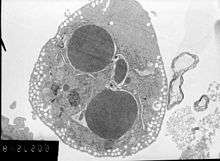

Neonatal cardiomyocytes ultrastructure after anoxia-reoxygenation.